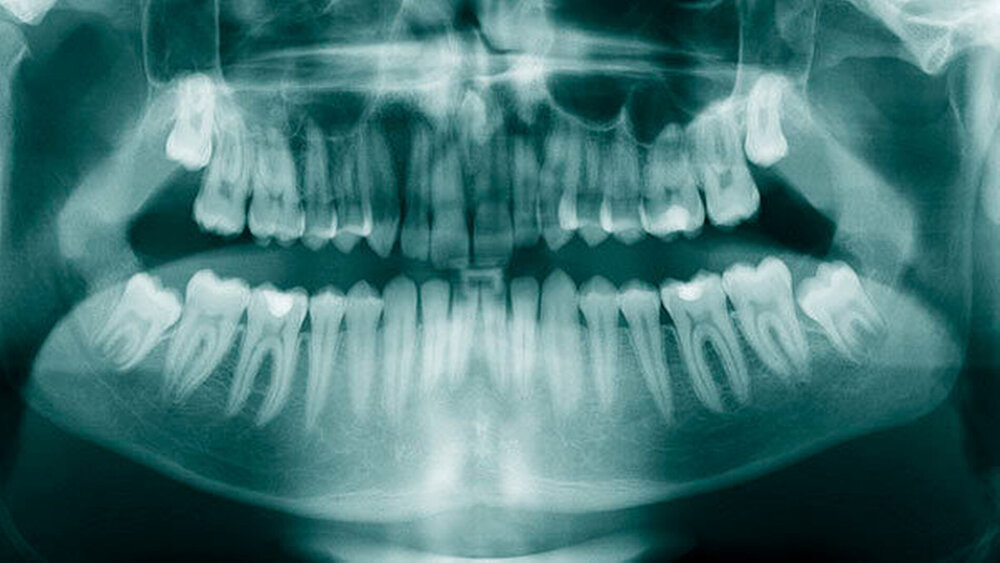

Überzählige Zähne können einzeln oder multipel auftreten [von Arx, 1990; Rajab Hamdan, 2002; Fernández Montenegro et al., 2006; Liu et al., 2007; Gündüz et al., 2008; Ferrés-Padró et al., 2009; Hyun et al., 2009]. Einzelne überzählige Zähne treten in 65,8 bis 80,5 Prozent, doppelte in 14,5 bis 27,7 Prozent und multiple in 0,6 bis 8 Prozent der Fälle auf [Rajab Hamdan, 2002; Fernández Montenegro et al., 2006; Liu et al., 2007; Ferrés-Padró et al., 2009; Hyun et al, 2009; Mossaz et al., 2014]. Einzelne oder doppelte überzählige Zähne finden sich typischerweise in der Oberkieferfront [Rajab Hamdan, 2002; Fernández Montenegroet al., 2006; Mossaz et al., 2014]. Multiple überzählige Zähne werden vor allem im Prämolarenbereich des Unterkiefers gefunden [Abbildung 4; YUSOF 1990, Ferrés-Padróet al., 2009; Wang Fan, 2011]. Multiple überzählige Zähne sind zudem oft mit anderen Erkrankungen oder Syndromen assoziiert, dazu gehören Lippen-Kiefer-Gaumenspalten, die cleidokraniale Dysplasie oder auch das Gardner-Syndrom. Bei Patienten mit einer Lippen-Kiefer-Gaumenspalte wird vermutet, dass sich die überzähligen Zähne aus der Fragmentierung der dentalen Lamina bei der Spaltbildung ergeben [Garvey et al., 1999; Wang Fan, 2011].